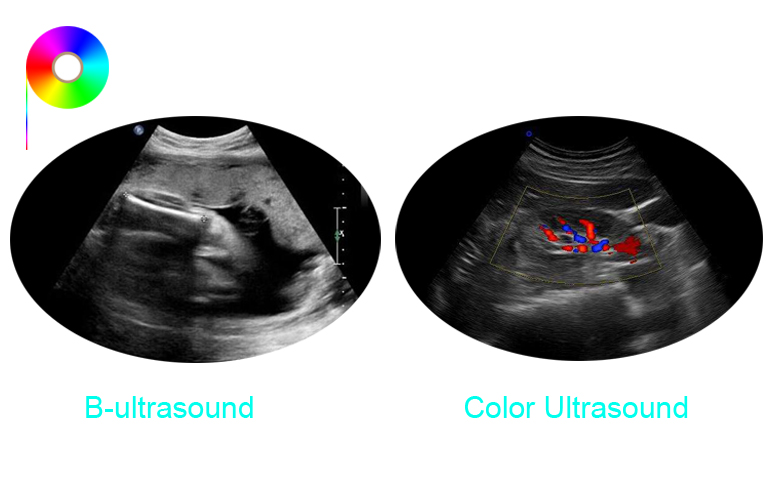

this article is a brief introduction to the difference between B-ultrasound and color ultrasound.